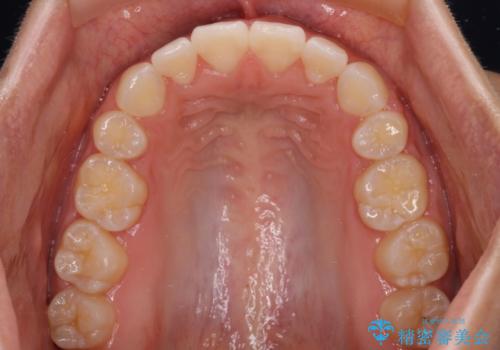

- 口が閉じにくさを気にして来院された患者様です。

上下の前歯が前方に突出していたため、上下左右の第一小臼歯4本を抜歯し、ワイヤー装置にて抜歯矯正を行うこととしました。

上下前歯部の被蓋関係を改善するの時間がかかり、3年間を要することとなりましたが、スッキリとした口元に仕上がりました。